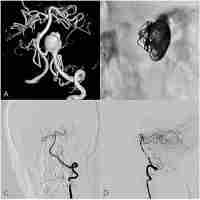

| Abstract | OBJECT: Use of a flow-diverting device has shown promising short-term results in the management of vertebral artery (VA) dissecting aneurysms, but there is still uncertainty regarding its long-term efficacy and safety. The authors report their initial experience with respect to the potential utility and long-term clinical outcomes of using a flow-diverting device in the treatment of unruptured dissecting VA aneurysms. METHODS: The authors conducted a retrospective review of all cases of unruptured intracranial VA dissecting aneurysms treated at their institution (Tuen Mun Hospital) with a flow-diverting device. They describe the clinical presentations and angiographic features of the cases and report the clinical outcome (with modified Rankin Scale [mRS] scores) at most recent follow-up, as well as results of the latest angiographic assessment, with particular focus on in-stent patency and side-branch occlusion. RESULTS: A total of 4 aneurysms were successfully obliterated by using flow-diverting devices alone. Two devices were deployed in a telescoping fashion in each of 2 aneurysms, whereas only 1 device was inserted in each of the other 2 aneurysms. No periprocedural complication was encountered. No patient showed any angiographic evidence of recurrence, in-stent thrombosis, or side-branch occlusion in angiographic reassessment at a mean of 22 months after treatment (range 18-24 months). As of the most recent clinical follow-up (mean 30 months after treatment, range 24-37 months), all patients had favorable outcomes (mRS Score 0). CONCLUSIONS: Reconstruction using a flow-diverting device is an attractive alternative in definitive treatment of dissecting VA aneurysms, demonstrating favorable long-term clinical and angiographic outcomes and the ability to maintain parent artery and side-branch patency. It is particularly useful in cases with eloquent side-branch or dominant VA involvement. |